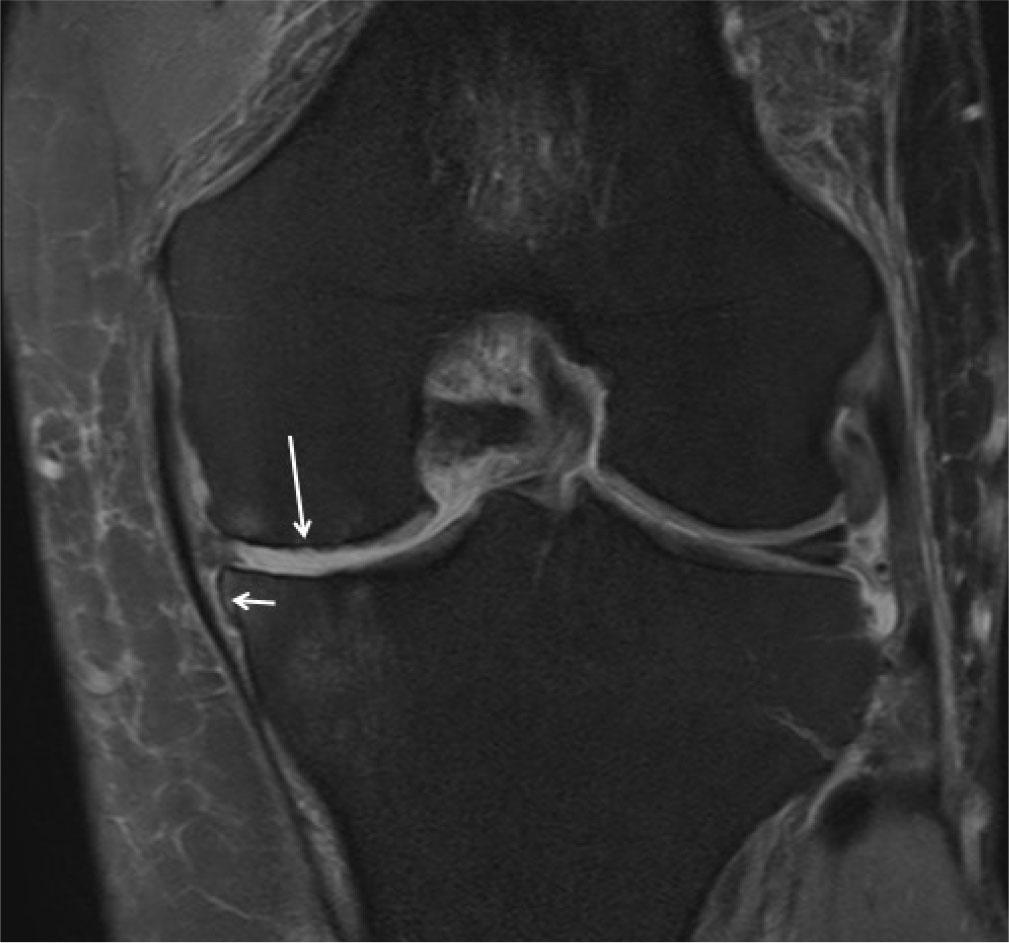

Fig. 23.

Osteoarthritis (OA): MR proton density fat-suppressed coronal image shows cartilage damage with cortical irregularity (long arrow) and osteophyte (small arrow). There is also tear of medial meniscus